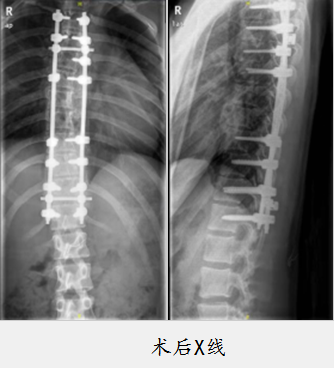

术中,董大明教授、关瑛副主任医师带领团队,以T3-T12为中心取后正中切口,在相应节段椎体安放椎弓根螺钉、金属棒,经过加压、植骨等步骤,胸椎生理后凸恢复,胸椎侧弯得以矫形,考虑到患者为14岁的女孩,董大明运用美容缝合,让刀口恢复后相对美观。术前侧弯角度(Cobb )为41度,术后0度,侧弯完全纠正,女孩整体状态良好。术后,骨科五病房张晓娟护士长带领护士结合ERAS理念,加速女孩术后康复,提高舒适度及满意度。